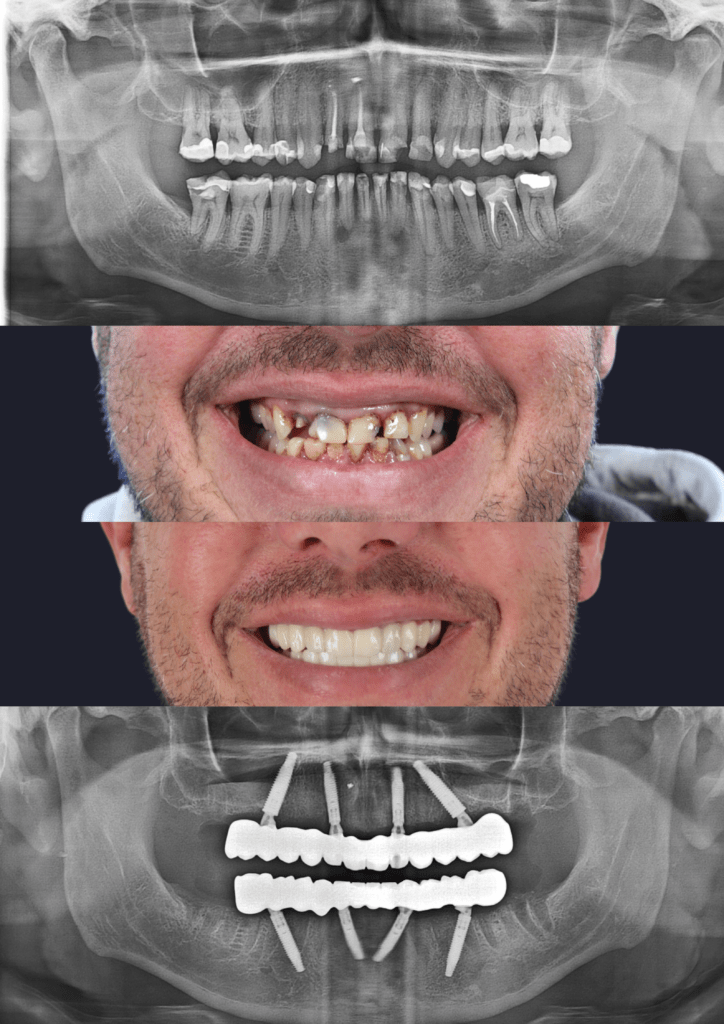

All-On-4® & All-On-X: Permanent Solutions for Full Arch Restoration in Adelaide

For patients missing all or most of their teeth in an arch, All-On-4® or similar “All-On-X” concepts provide a life-changing alternative to a removable denture. This advanced treatment uses as few as four strategically placed implants to support a full, permanent bridge of replacement teeth. This fixed solution restores nearly 100% of chewing function and provides the security and confidence that dentures simply cannot match. It is the ultimate service for a complete smile and jawbone restoration.